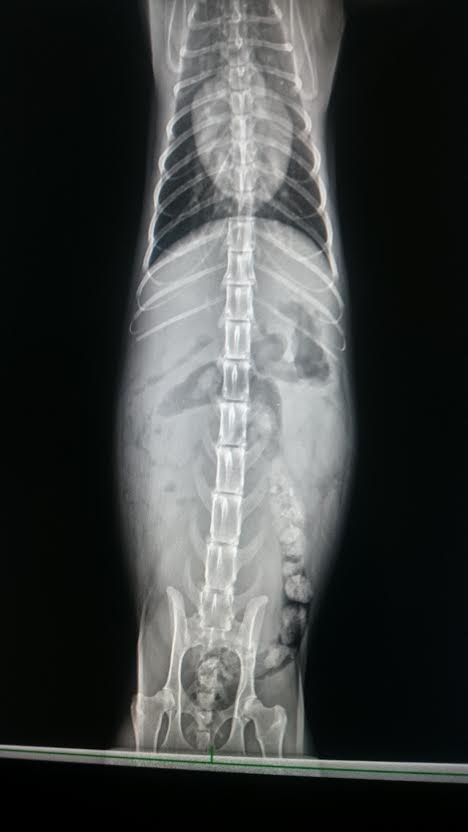

鐵蛋有貧血問題,肝腎指數皆偏高

且腎功能不全(多尿)

以及腎衰、膽結石,

1. 貧血,肝腎指數偏高,腎功能不全(多尿)